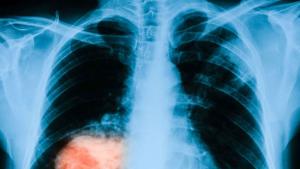

Триизмерна "пътна карта" улеснява откриването на белодробен рак

Сингапурски специалисти са разработили и тествали нова процедура, която помага на ...